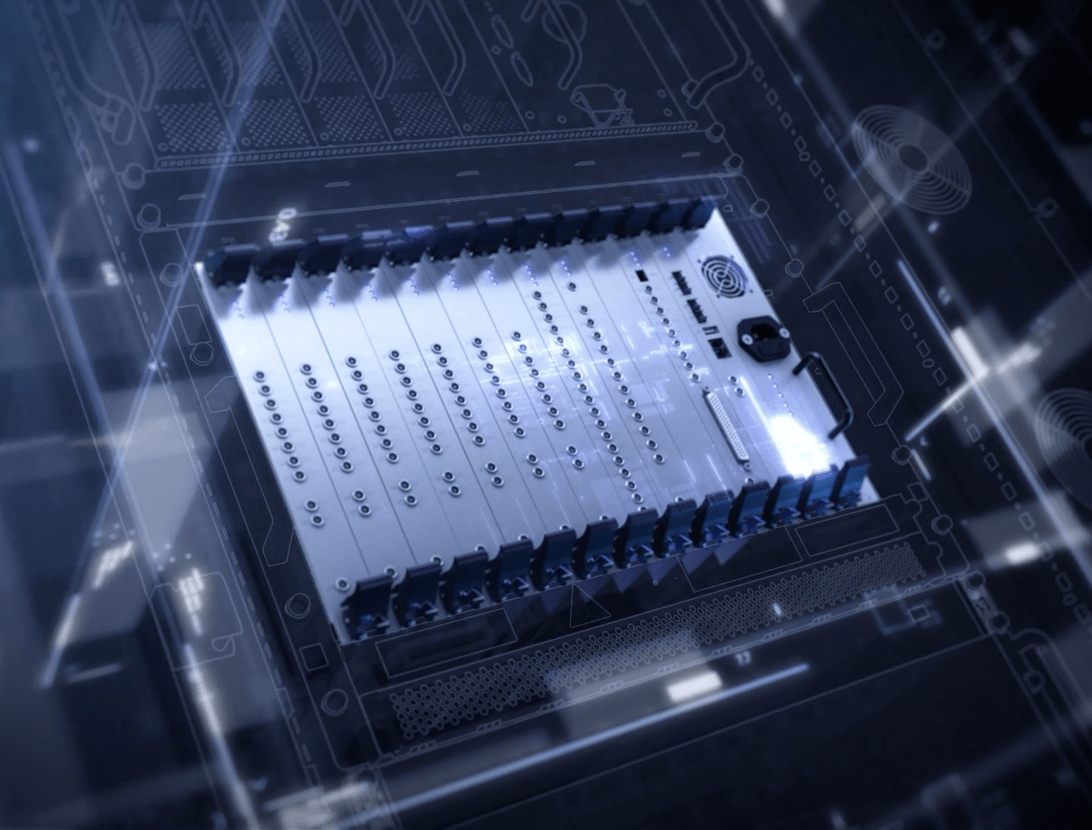

「3.0T级」高性能射频

uMR 680突破传统射频接收架构限制,支持独立72+通道射频接收平台,构建起真正的超高通道、超高速全数字传输通路,同时,基于AI深度学习图像重建技术的完美融合,从数据采集、数据传输、数据运算、数据重建全链条赋能,让高清影像轻松可得。